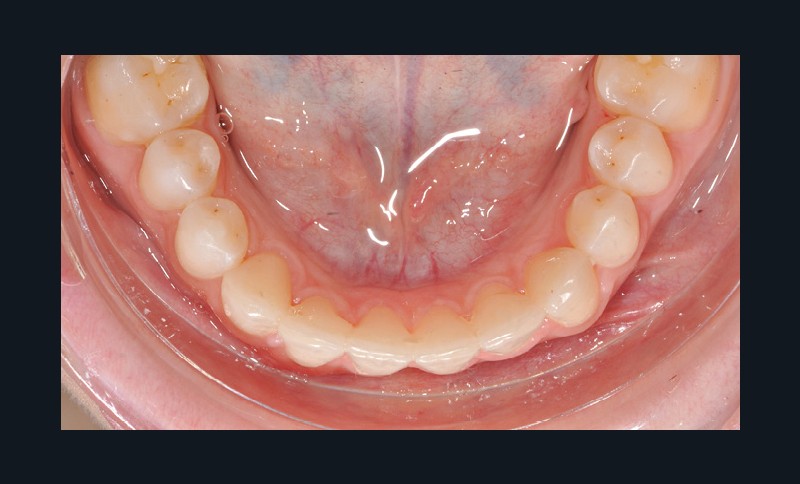

Par exemple, le retraitement d’un patient atteint d’un « Syndrome du fil » [2, 3], au vu de l’état des connaissances imparfaites de l’étiologie de cette situation, méritera une réflexion pour trouver un système de confiance. Une fibre collée est l’une des solutions sécurisantes (fig. 1). Mais, si la langue n’est pas stabilisée au repos comme en fonction, un dispositif amovible type Spring Retainer sera préférable.